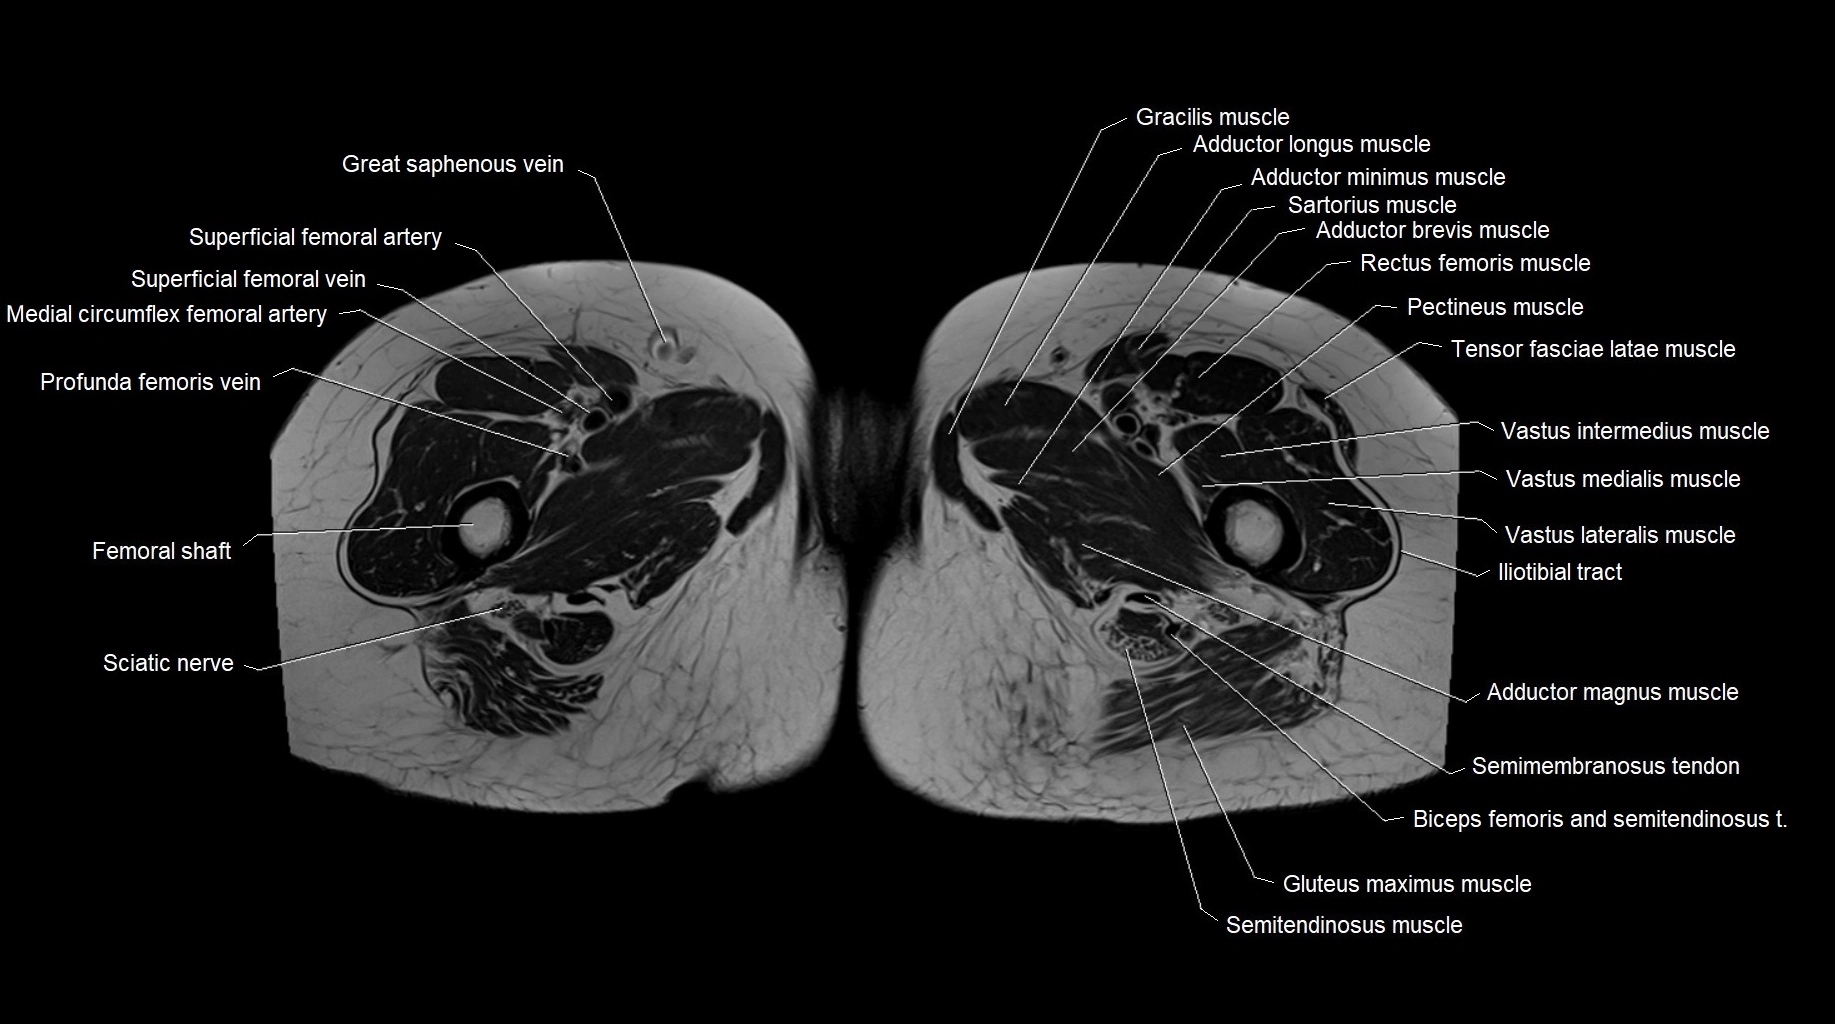

- Femoral shaft

- Gracilis muscle

- Adductor brevis muscle

- Adductor longus muscle

- Adductor magnus muscle

- Adductor minimus muscle

- Sciatic nerve

- Vastus intermedius muscle

- Vastus lateralis muscle

- Vastus medialis muscle

- Iliotibial tract

- Sartorius muscle

- Rectus femoris muscle

- Pectineus muscle

- Tensor fasciae latae muscle

- Medial circumflex femoral artery

- Superficial femoral artery

- great saphenous vein